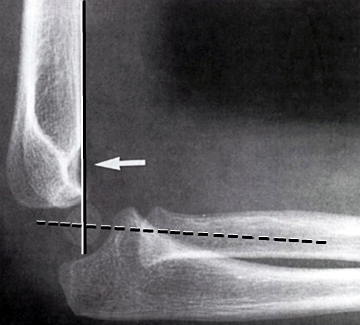

En linie gennem centrum af radius skal altid gå lige igennem capitulum humeri.

En linie langs forsiden af humerus går normalt igennem midterste 1/3 del af capitulum humeri, hvis capitulum ligger bagved skal der reponeres og osteosynteres i GA. Hos børn under 4 år tillades lidt større dislokation.

BOWING ULNA:

Normal:

Bemærk dislocation af radius. Skal reponeres i GA.